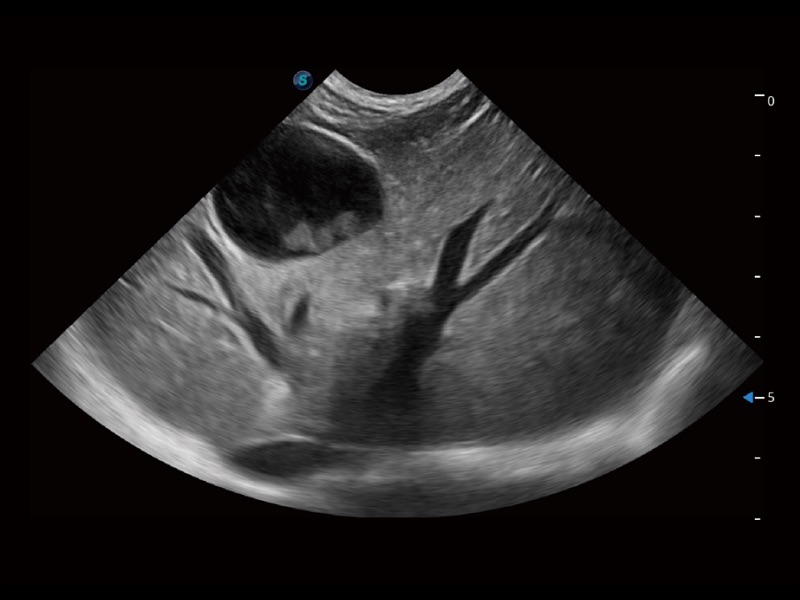

优异的基础图像

ProPet 70 全新的动物超声智能软件和丰富的探头群,为动物医生提供了高清晰度和精细分辨率的图像,无论在宠物、马科、畜牧还是实验室动物等应用中都可以轻松应对,为您的日常工作带来满意的体验。

(犬)肾脏显微血流

(猫)胆囊

(猫)肺动脉血流频谱

(犬)左室长轴血流

(犬)髂动脉血流

(犬)四腔心

(犬)胎儿主动脉弓立体血流

(犬)肝脏

(犬)四腔心MQA